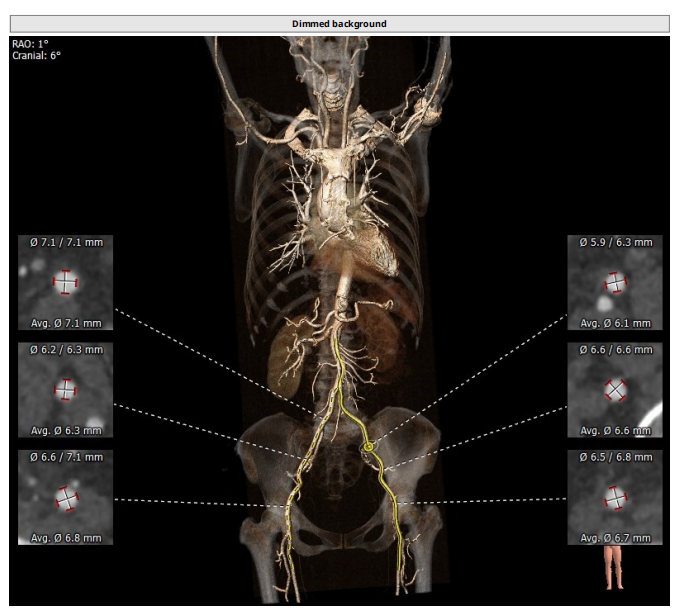

瓣环:16.9mm;左室流出道:16.7mm

STJ:23.9mm;升主动脉:31.4mm

工作体位:LAO:12°CRA:5° ;左冠切线位:LAO:26° CRA:19°

右股为主入路

患者为三叶瓣,左右、右无疑似粘连,瓣叶明显增厚,轻度钙化。右冠高度10.9mm,左冠高度9.5mm,冠脉高度均较低。法式窦小,心脏角度不大,左室大小可,升主动脉未见明显增宽,病人整体结构小,瓣环仅有16.9mm,左室流出道16.7mm,窦管结合部23.9mm,升主动脉31.4mm。选择右股作为主入路。